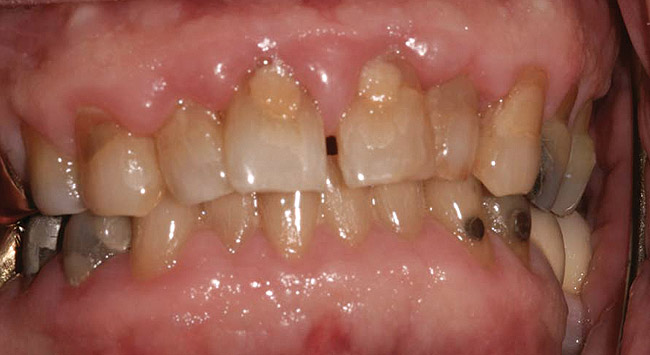

Fig 2. A 42-year-old male patient with good oral hygiene, taking 30 mg nifedipine daily, with signs of generalized gingival enlargement. (photo courtesy of Asim Alsuwaiyan, BDS)

Figure 2

Such theories remain speculative, since it has not been possible to demonstrate whether changes in microflora are the cause or the effect of the enlargement. As noted by Modéer et al29 and Nery et al,30 plaque would act as a co-factor, since drug-induced gingival overgrowth is also observed in patients with excellent oral hygiene. Consequently, the authors concluded that rigorous plaque control in patients treated with certain drugs can limit the severity of lesion development but cannot prevent it altogether (Figure 2).